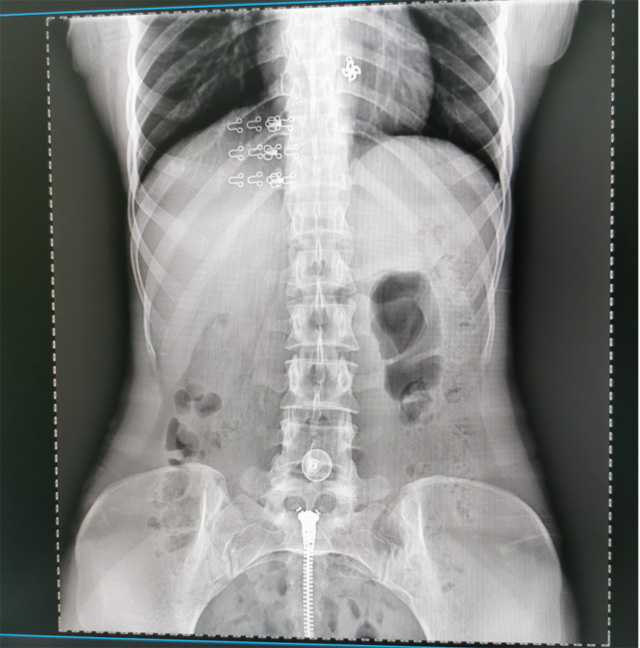

提高医院的影像科的医疗服务水平,满足满足人民群众不断增长的医疗需求,促进医疗技术快速发展。医院都引进悬吊DR拍片设备新一代数字化X线摄影系统。标志着医院的诊疗水平又上升一个新的台阶。悬吊DR满足人体头部、胸部、腹部、腰椎、四肢等部位的数字摄影检查,可以检查呼吸系统疾病,心脏系统的疾病、骨关节系统的疾病,子宫输卵管造影、胃肠道造影,.有职业病体检筛查尘肺病功能。通过DR数字化摄影,分段连续、重叠采集数字化图像,利用软件对图像进行拼接的方式来获得全脊柱、全上肢或全下肢的图像。新设备的图像更清晰,临床拍摄避免患者再次搬运和移动产生的痛苦,是创伤骨折患者的福音。辐射减少受照剂量50%,后处理能力强、图像质量高。有效降低操作难度,缩短工作流程,尤其适合大批量体检。

具有射线剂量小、图像清晰度高、误差小等特点,悬吊DR已广泛应用于各级医疗机构的体检中心,越来越受到临床医生的肯定和患者的青睐。为临床诊断工作提供更加直观有效的技术支持,大大提高了患者就医效率从而为患者提供更加优质的医疗服务。提高了其成像质量和临床应用价值,并极大减少了受照辐射剂量。有效满足了各种常见疾病的临床诊断和治疗需求。以医疗质量为根本,以优质服务为导向,竭诚为人民群众的健康保驾护航。